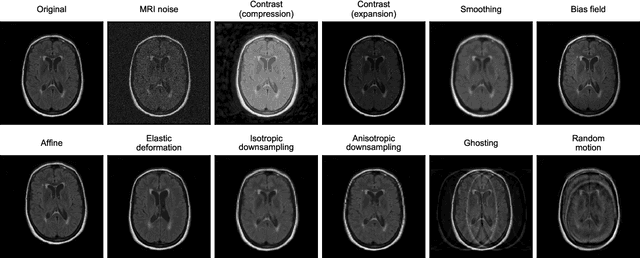

Abstract:Deep artificial neural networks (DNNs) have moved to the forefront of medical image analysis due to their success in classification, segmentation, and detection challenges. A principal challenge in large-scale deployment of DNNs in neuroimage analysis is the potential for shifts in signal-to-noise ratio, contrast, resolution, and presence of artifacts from site to site due to variances in scanners and acquisition protocols. DNNs are famously susceptible to these distribution shifts in computer vision. Currently, there are no benchmarking platforms or frameworks to assess the robustness of new and existing models to specific distribution shifts in MRI, and accessible multi-site benchmarking datasets are still scarce or task-specific. To address these limitations, we propose ROOD-MRI: a platform for benchmarking the Robustness of DNNs to Out-Of-Distribution (OOD) data, corruptions, and artifacts in MRI. The platform provides modules for generating benchmarking datasets using transforms that model distribution shifts in MRI, implementations of newly derived benchmarking metrics for image segmentation, and examples for using the methodology with new models and tasks. We apply our methodology to hippocampus, ventricle, and white matter hyperintensity segmentation in several large studies, providing the hippocampus dataset as a publicly available benchmark. By evaluating modern DNNs on these datasets, we demonstrate that they are highly susceptible to distribution shifts and corruptions in MRI. We show that while data augmentation strategies can substantially improve robustness to OOD data for anatomical segmentation tasks, modern DNNs using augmentation still lack robustness in more challenging lesion-based segmentation tasks. We finally benchmark U-Nets and transformer-based models, finding consistent differences in robustness to particular classes of transforms across architectures.